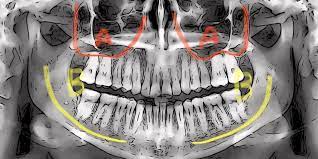

임플란트는 턱뼈에 임플란트 자체를 묻는 치료입니다. 특히 하악의 뼈 중에는 굵은 신경과 혈관이 지나가는 하치조관이 존재하는데 하치조관의 신경을 만지면 신경이 손상되거나 끊어질 수 있습니다.

임플란트 치료에 있어서 신경 손상의 확률은 0.13~8.5% 로 높은 편입니다.

최근에는 임플란트 치료 전문 치과 치료소의 대부분에서 CT를 도입하고 3D 이미지에서 신경의 위치를 확인하는 등 신경 손상의 위험을 줄이기 위해 노력하고 있습니다.

신경이 손상되면 입 주의와 혀 감각의 마비와 흉터가 생깁니다. 실제로 신경에 손상이 없어도 임플란트가 신경 근처에 있어 신경을 압박하는 경우에도 증상이 나타날 수 있습니다.

만약에 마비 등의 증상이 나오면 ATP, 비타민B12, 스테로이드 등의 투약으로 개선이 가능하나 개선이 되지 않는다면 임플란트를 다시 제거해야 됩니다.